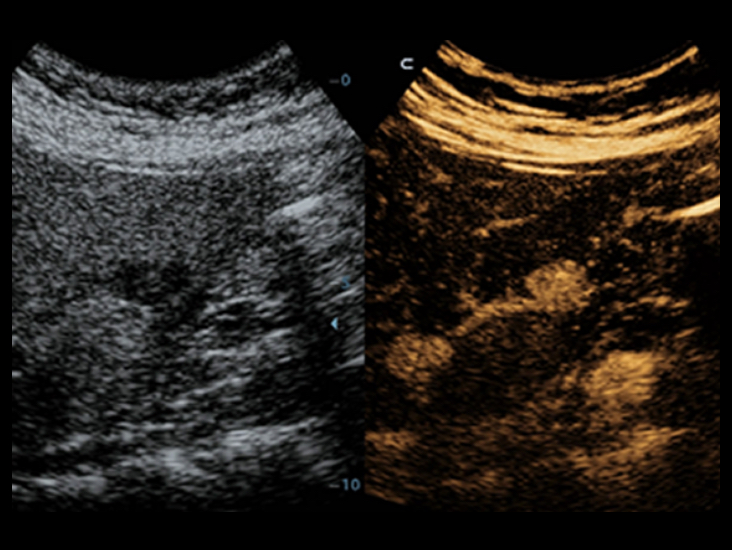

–€–Ψ―²–Η–≤–Α―Ü–Η―è –Κ–Ψ–Φ–Ω–Α–Ϋ–Η–Η Mindray –Ζ–Α–Κ–Μ―é―΅–Α–Β―²―¹―è –≤ –Ϋ–Β–Ω―Ä–Β―Ä―΄–≤–Ϋ–Ψ–Φ –≤–Ϋ–Β–¥―Ä–Β–Ϋ–Η–Η –Η–Ϋ–Ϋ–Ψ–≤–Α―Ü–Η–Ι. –ë–Μ–Α–≥–Ψ–¥–Α―Ä―è –¥–Η―¹–Ω–Μ–Β―é Full HD, –Κ–Μ–Α―¹―¹–Η―΅–Β―¹–Κ–Η–Φ ―²–Β―Ö–Ϋ–Ψ–Μ–Ψ–≥–Η―è–Φ –¥–Μ―è –Ω–Ψ–Μ―É―΅–Β–Ϋ–Η―è –Η –Ψ–±―Ä–Α–±–Ψ―²–Κ–Η –Η–Ζ–Ψ–±―Ä–Α–Ε–Β–Ϋ–Η–Ι –Η –Ψ–Ω―²–Η–Φ–Η–Ζ–Η―Ä–Ψ–≤–Α–Ϋ–Ϋ–Ψ–Φ―É ―¹–Β–Φ–Β–Ι―¹―²–≤―É –¥–Α―²―΅–Η–Κ–Ψ–≤ ―¹–Η―¹―²–Β–Φ–Α DC-40 ―¹ Full HD –Ψ–±–Β―¹–Ω–Β―΅–Η–≤–Α–Β―² –Ϋ–Β–Ω―Ä–Β–≤–Ζ–Ψ–Ι–¥–Β–Ϋ–Ϋ―É―é ―΅–Β―²–Κ–Ψ―¹―²―¨ –Η–Ζ–Ψ–±―Ä–Α–Ε–Β–Ϋ–Η–Ι –¥–Μ―è –±–Ψ–Μ–Β–Β ―à–Η―Ä–Ψ–Κ–Ψ–≥–Ψ ―¹–Ω–Β–Κ―²―Ä–Α –Ψ–±–Μ–Α―¹―²–Β–Ι –Ω―Ä–Η–Φ–Β–Ϋ–Β–Ϋ–Η―è.

–ë–Μ–Α–≥–Ψ–¥–Α―Ä―è –Ω―Ä–Η–Φ–Β–Ϋ–Β–Ϋ–Η―é –Κ–Μ–Α―¹―¹–Η―΅–Β―¹–Κ–Η―Ö ―²–Β―Ö–Ϋ–Ψ–Μ–Ψ–≥–Η–Ι –Ψ–±―Ä–Α–±–Ψ―²–Κ–Η ―¹–Η–≥–Ϋ–Α–Μ–Α, –Κ–Ψ―²–Ψ―Ä―΄–Β –±―΄–Μ–Η –Ζ–Α–Η–Φ―¹―²–≤–Ψ–≤–Α–Ϋ―΄ –Η–Ζ ―¹―É―â–Β―¹―²–≤―É―é―â–Η―Ö ―É–Μ―¨―²―Ä–Α–Ζ–≤―É–Κ–Ψ–≤―΄―Ö ―¹–Η―¹―²–Β–Φ, DC-40 ―¹ Full HD –Ω―Ä–Β–¥–Μ–Α–≥–Α–Β―² –≤―΄―¹–Ψ―²–Ψ–Β –Κ–Α―΅–Β―¹―²–≤–Ψ –¥–Β―²–Α–Μ–Η–Ζ–Α―Ü–Η–Η –Ω–Ψ–Μ―΅–Α–Β–Φ―΄―Ö –Η–Ζ–Ψ–±―Ä–Α–Ε–Β–Ϋ–Η–Ι.

–ë–Μ–Α–≥–Ψ–¥–Α―Ä―è ―à–Η―Ä–Ψ–Κ–Ψ–Φ―É ―¹–Ω–Β–Κ―²―Ä―É –Ω–Ψ–¥–¥–Β―Ä–Ε–Η–≤–Α–Β–Φ―΄―Ö –¥–Α―²―΅–Η–Κ–Ψ–≤ DC-40 ―¹ Full HD –Ψ–±–Β―¹–Ω–Β―΅–Η–≤–Α–Β―² ―É–Ϋ–Η–≤–Β―Ä―¹–Α–Μ―¨–Ϋ–Ψ―¹―²―¨ –Η –≤―΄―¹–Ψ–Κ―É―é –Ω―Ä–Ψ–Η–Ζ–≤–Ψ–¥–Η―²–Β–Μ―¨–Ϋ–Ψ―¹―²―¨ –¥–Μ―è –≤―¹–Β―Ö –Ψ–±–Μ–Α―¹―²–Β–Ι –Ω―Ä–Η–Φ–Β–Ϋ–Β–Ϋ–Η―è, –Α ―²–Α–Κ–Ε–Β –≤―΄―¹–Ψ–Κ–Ψ–Β –Κ–Α―΅–Β―¹―²–≤–Ψ –≤–Η–Ζ―É–Α–Μ–Η–Ζ–Α―Ü–Η–Η –¥–Μ―è ―Ä–Α–Ζ–Ϋ―΄―Ö ―²–Η–Ω–Ψ–≤ –Ω–Α―Ü–Η–Β–Ϋ―²–Ψ–≤.